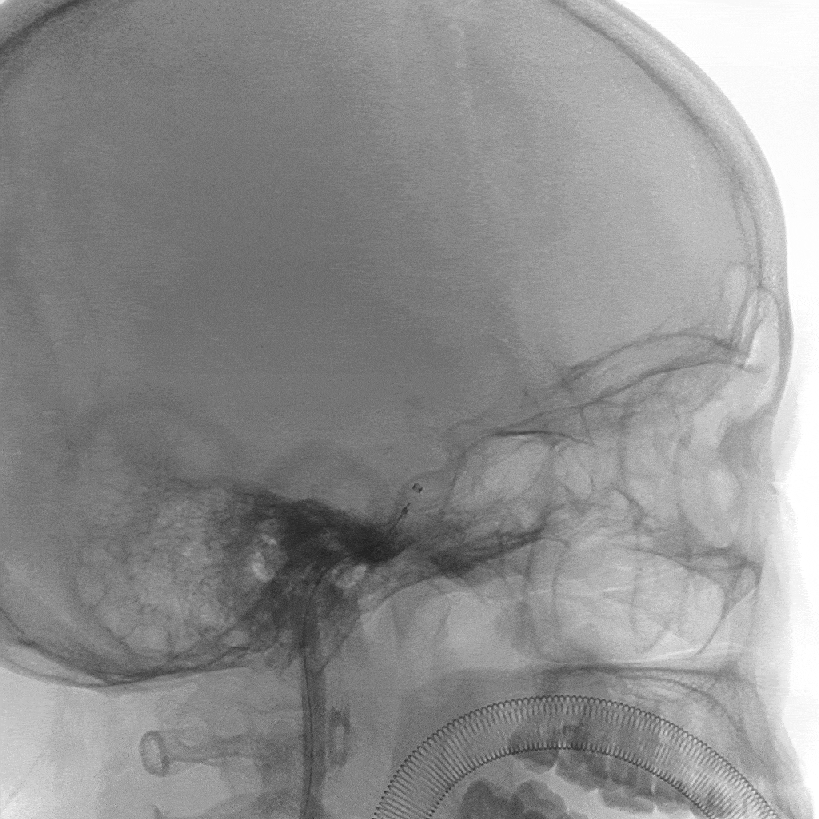

2021-12-20 脑血管造影:

左侧颈内动脉多发动脉瘤;右侧颈内动脉床突段动脉瘤。

LICA 多发动脉瘤,大小分别为3.09×3.79mm、1.73×1.73m及1.79mm×1.63mm,载瘤动脉远端直径为3.11mm,近端直径3.49mm。

RICA 床突旁动脉瘤 6.56×5.29mm ,载瘤动脉近段直径约3.66mm,远端直径3.40mm。